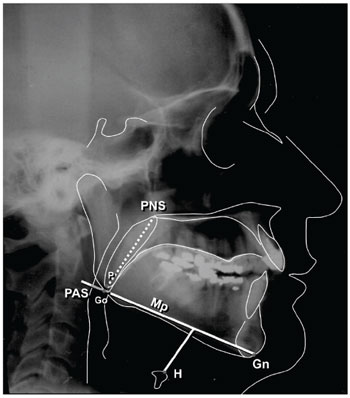

The following cephalometric traces were considered, since they are the most commonly used cephalometric measures: retroglossal posterior airway space (PAS), defined as the space between the base of the tongue and the posterior pharyngeal wall; the distance between the mandibular plane and the hyoid bone (MP-H); the SNA angle, formed by the junction between the sellar point (S, midpoint of the sella turcica), nasion (N, junction between the frontal and nasal bones), and point A (deepest concavity on the anterior profile of the maxilla); the SNB angle, formed by the junction between the sellar point (S), nasion (N), and point B (deepest concavity on the anterior profile of the mandibular symphysis); the distance between the posterior nasal spine and the tip of the soft palate (PNS-P); and the difference between SNA and SNB (ANB) (Figure 1) (8,9,12,15).

Figure 1. Description of cephalometric parameters (Source: the author).